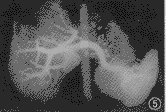

图4 肝癌伴门静脉癌栓。门静脉主干明显增粗,与近端血管不成比例,左支、主干及右支内均可见充盈缺损(癌栓),食管胃底静脉曲张

4.肝硬化门脉高压患者侧支循环CTP表现:在125例肝硬化患者中存在侧支循环者41例,多数病例存在2个或2个以上部位侧支循环,包括食管胃底静脉曲张(35例)、脾门周围静脉曲张(19例)、脐静脉开放(10例)、脾肾静脉自发分流(9例)、胆囊周围静脉曲张(4例),CTP除能显示侧支循环外,于4例肝硬化患者门静脉主干内尚见血栓形成(图6)。